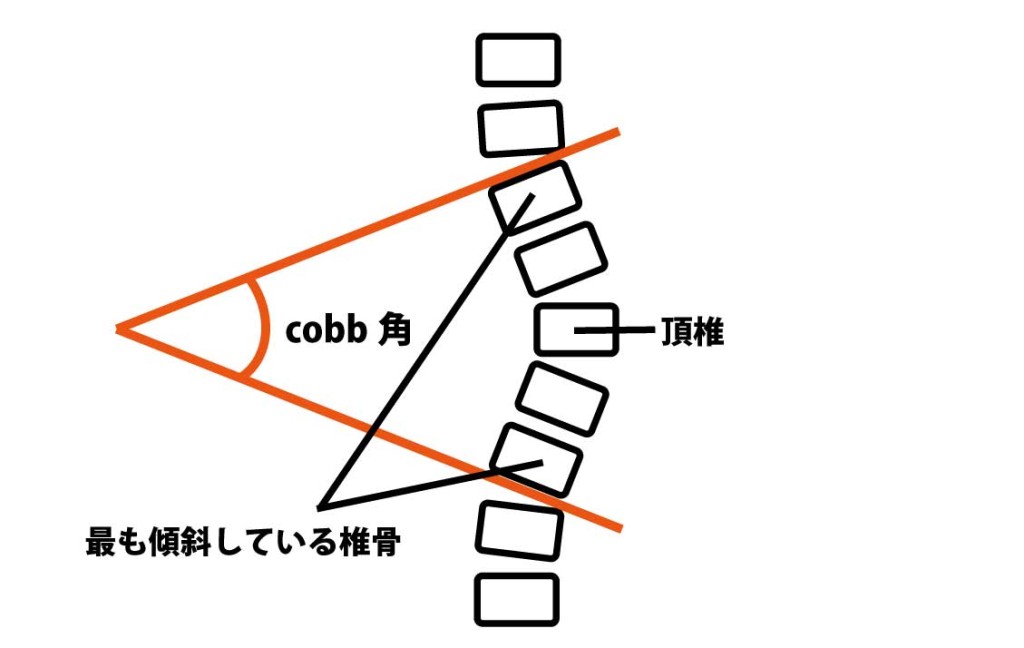

Cobb角:終椎(上端・下端椎)の終板に引いた接線の交角。

Cobb角:側弯の角度評価の基本指標。